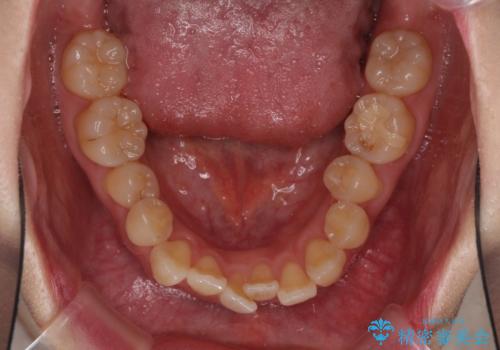

ハーフリンガル 反対咬合の改善

- 前歯の反対咬合を気にして来院された患者様です。

目立ちにくい装置での治療をご希望とのことで、上顎が裏側装置、下顎が表側装置のハーフリンガルにより矯正治療を行うこととしました。

下顎の歯列全体を後方に動かす場合、さまざまリスクを伴うため慎重に行う必要があり、さらには移動量に限界があるため、治療計画は無理のないものとしなければなりません。

下顎左右の奥にアンカーボルトを使用して、無理のない範囲で後方に移動させ、きれいに仕上げることができました。